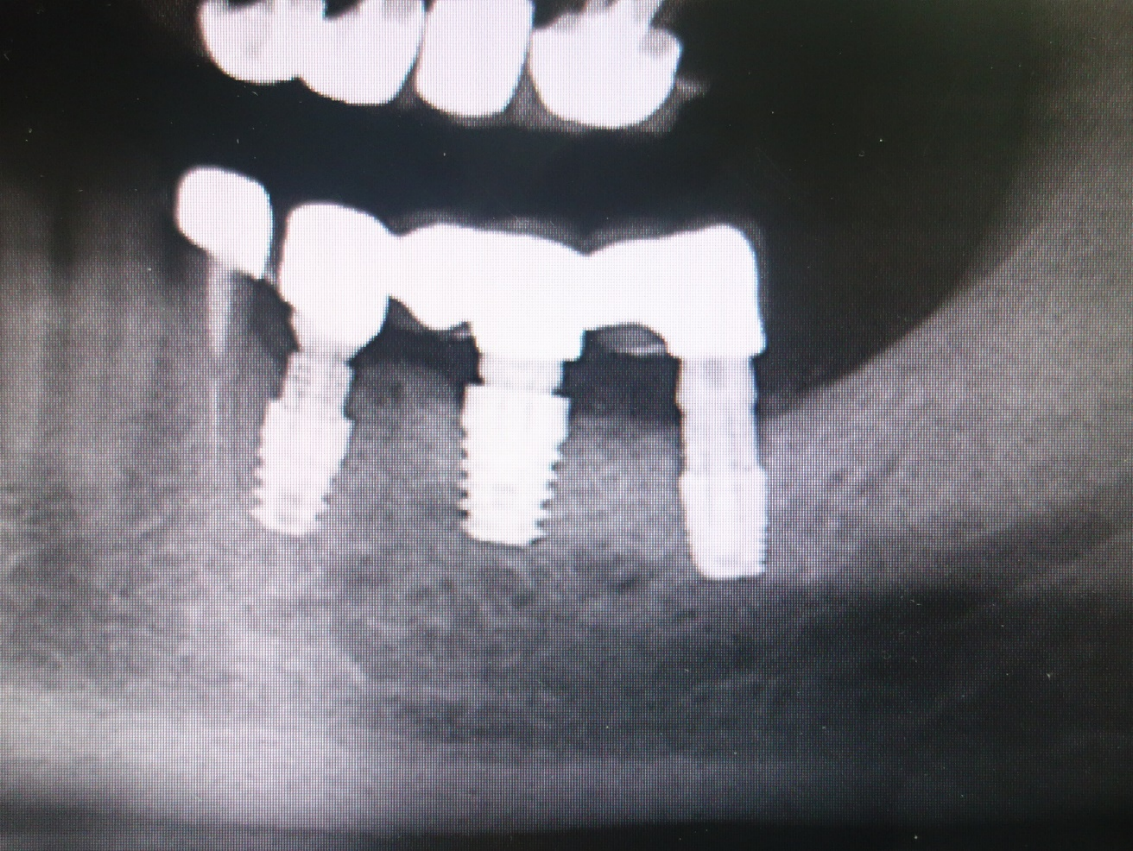

Case 17

Implant and teeth extraction. Placing the universal plus implant.